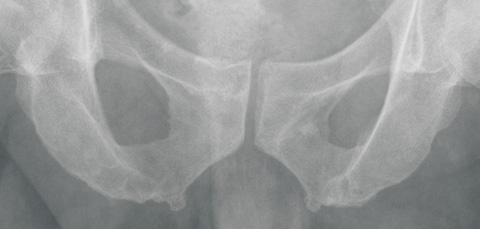

When the remains at St Thomaskirche were transferred to a new coffin in 1949, surgeon Wolfgang Rosenthal had the opportunity to inspect the skeleton. Although he did not notice any special features of the skull, he detected multiple bony outgrowths, which he considered to be exostoses, on the pelvic ring.3 He claimed His had mistaken these for signs of “arthrosis deformans” (osteoarthritis). He also noticed overdeveloped Muskellinien (“muscle lines”; bony outgrowths at sites of muscle and ligament attachment, now termed enthesophytes) on the arms of the skeleton. These outgrowths were assumed to be a sign of physical strength in people who use their arms powerfully over a long period. Rosenthal stated that multiple exostoses on the arms and legs are generally found in horseback riders, soldiers and sportsmen, in response to repetitive mechanical trauma. At that time, such formations were termed Reiter- und Exerzierknochen (“horseback rider and military drill bones”). A modern interpretation of these lesions is shown in Box 2.

A second part of our investigation was to reproduce the research reported by Rosenthal. We undertook a study to explore the presence of enthesophytes in modern-day organists. Details are shown in Box 3.

In 1949, surgeon Wolfgang Rosenthal noticed exostoses on the skeleton and on x-rays of 11 living organists and proposed a condition, Organistenkrankheit, which he interpreted as evidence that the skeleton was Bach’s.

Also, our study of the pelvic x-rays of 12 living professional organists failed to find evidence for the existence of Organistenkrankheit.